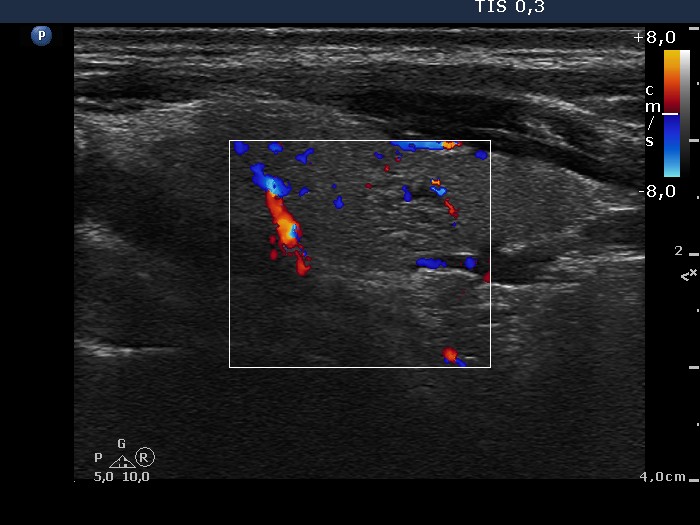

100 consecutive cases of papillary cancer - case 040 (ultrasonographic picture 6)

Left lobe, longitudinal view, color Doppler mode. The lesion presents signs of perinodular and intranodular blood flow.